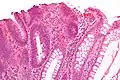

| Тип полипа | Гистологическое строение | Риск злокачественного развития | Микроснимок[3] | Синдром |

| Трубчатая аденома | Трубчатые железы с удлинёнными ядрами (как минимум незначительная атипия) | Да | ![]() |

|